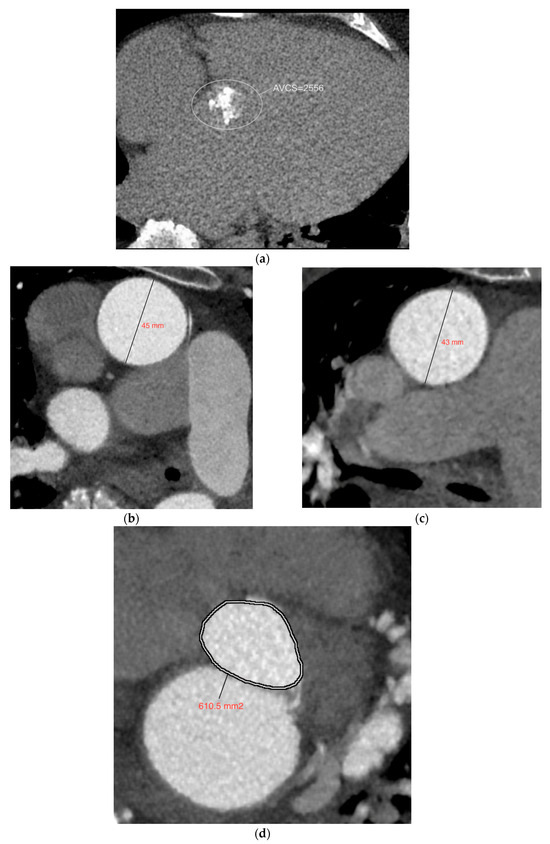

Assessment of Potential Predictors of Aortic Stenosis Severity Using ECG-Gated Multidetector CT in Patients with Bicuspid and Tricuspid Aortic Valves Prior to TAVI

Background/Objectives: The aim of this study was to evaluate the usefulness of selected predictive parameters obtainable from cardiac multidetector computed tomography for assessing the severity of aortic valve stenosis in patients scheduled for transcatheter aortic valve implantation (TAVI). Methods: A detailed [...] Read more.

Background/Objectives: The aim of this study was to evaluate the usefulness of selected predictive parameters obtainable from cardiac multidetector computed tomography for assessing the severity of aortic valve stenosis in patients scheduled for transcatheter aortic valve implantation (TAVI). Methods: A detailed retrospective analysis was performed on 105 patients with a bicuspid aortic valve (BAV), selected from a cohort of 1000 patients with BAV confirmed on ECG-gated CT, and on 105 patients with a tricuspid aortic valve (TAV) matched for sex and age. All patients included in both groups had significant aortic stenosis confirmed on transthoracic echocardiography. Results: Across the entire cohort, a trend toward higher aortic valve calcium scores was observed in patients with bicuspid compared to tricuspid aortic valves (4194.8 ± 2748.7 vs. 3335.0 ± 1618.8), although this difference did not reach statistical significance (p = 0.080). However, sex-stratified analysis showed higher calcium scores in males with BAV than with TAV (5596.8 ± 2936.6 vs. 4061.4 ± 1659.8, p = 0.002), with no significant difference observed among females (p > 0.05). Univariate regression analysis showed that the aortic valve calcium score was the strongest statistically significant predictor of aortic stenosis severity in both groups, with R2 = 0.224 for BAV and R2 = 0.479 for TAV. In the multiple regression model without interaction terms, the explanatory power increased to R2 = 0.280 for BAV and R2 = 0.495 for TAV. Conclusions: In patients scheduled for TAVI, linear regression models assess the severity of aortic stenosis more accurately than any individual predictive parameter obtainable from ECG-CT, with the aortic valve Agatston score emerging as the most reliable single CT-derived predictor of stenosis severity in both TAV and BAV subgroups. Full article

(This article belongs to the Special Issue Advances in Cardiovascular Computed Tomography (CT))

Show Figures

Figure 1